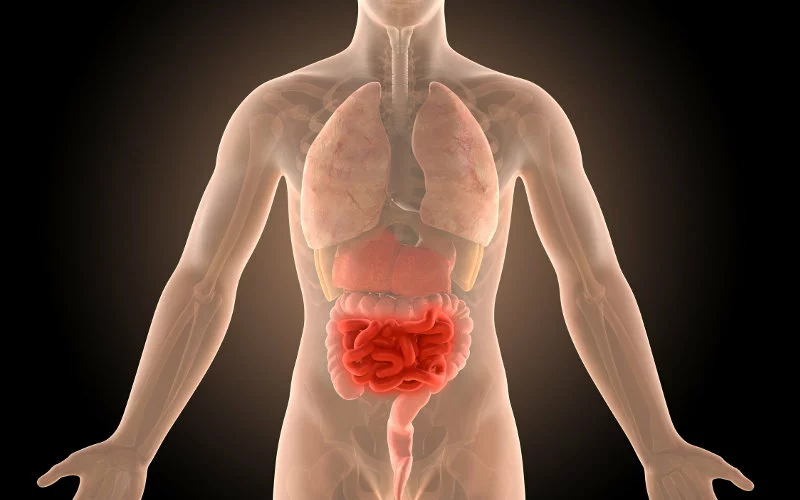

Αν και η ακριβής αιτία της νόσου είναι άγνωστη, η κατάσταση επηρεάζει τον γαστρεντερικό σωλήνα και συχνά οδηγεί σε φλεγμονή του λεπτού και του παχέος εντέρου.